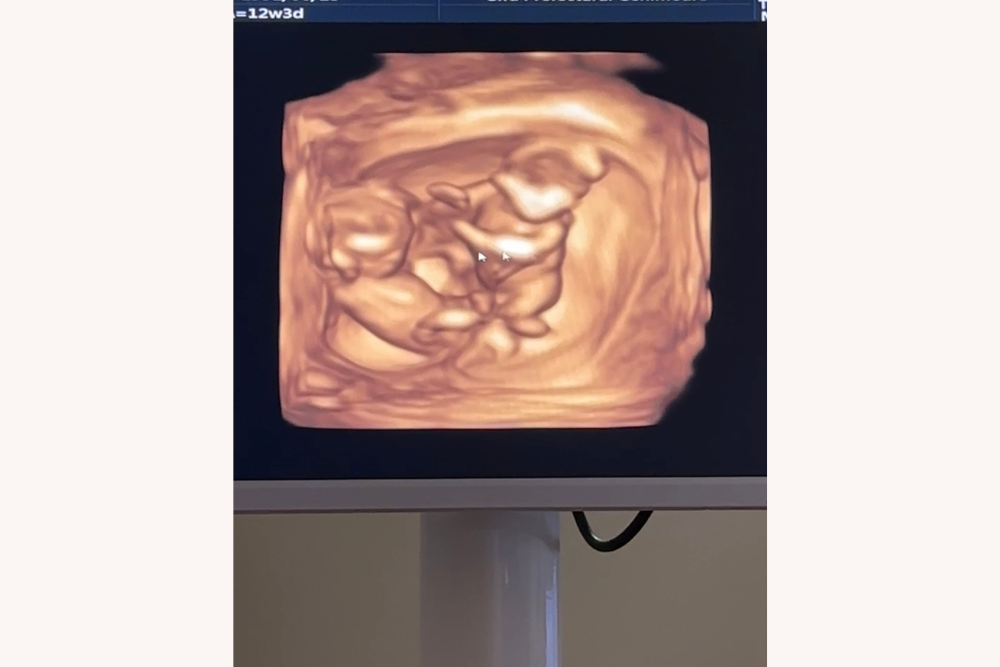

その後、移植した2つの受精卵は無事に着床し、双子を妊娠することができたんです。

4Dエコーで双子の赤ちゃんたちがしっかり確認できた!不安よりも喜びが大きかった。